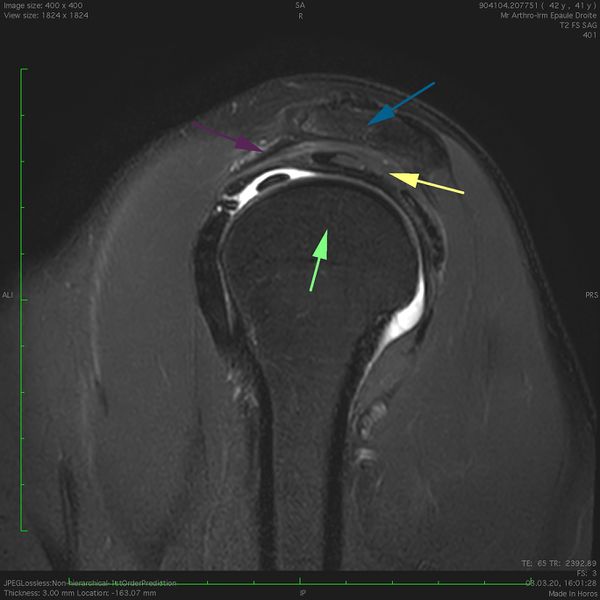

Magnetic resonance imaging (MRI) T2 fat saturation sagittal view of a right subacromial space. The acromion superiorly (blue arrow), the coracoacromial ligament anteriorly (purple arrow) and the humeral head inferiorly (green arrow) surround the supraspinatus tendon (yellow arrow). Note: anterior is the left in the image.